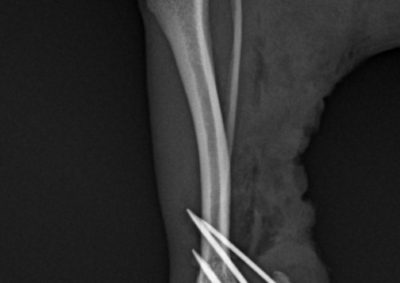

整形外科軟部組織外科

アキレス腱断裂